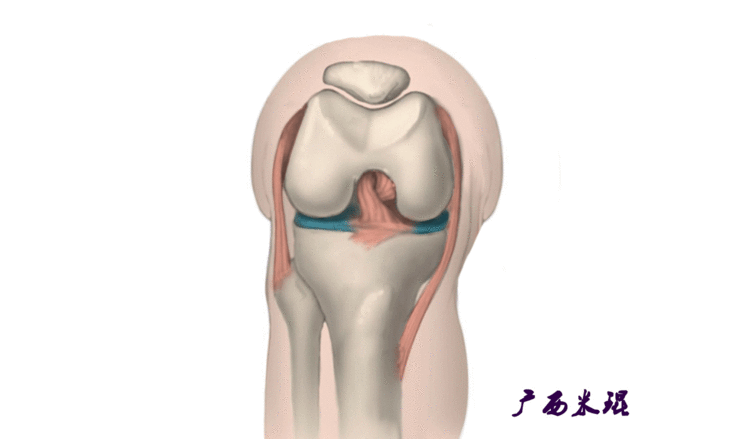

髌骨脱位绝大部分是向外侧脱位,脱位后,髌股关节内侧的稳定结构,包括髌股关节内侧支持带、股内侧肌、内侧髌股韧带均被撕裂,导致膝关节腔内积肿,在髌骨脱位以及自行复位的过程中,髌骨内侧面与股骨髁外侧面撞击,会引起软骨损伤或骨软骨骨折,所以,千万不要把髌骨脱位当作成一个简单的疾病。